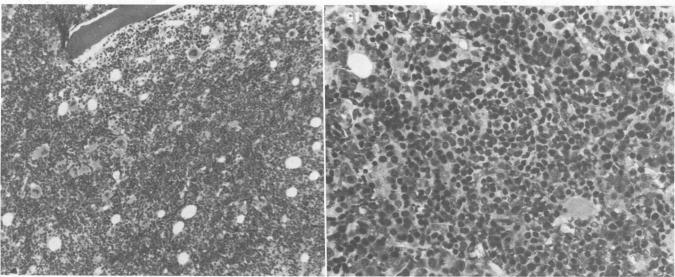

In reviewing the peripheral hematologic manifestations, bone marrow changes and clinical course in 41 consecutive patients with acquired immunodeficiency syndrome (AIDS), frequent findings included anemia (95%), leukopenia (76%), bone marrow hypercellularity (73%) and pancytopenia (41%). These hematologic abnormalities were not clearly associated with specific clinical manifestations of AIDS, but support the conclusion that the hematopoietic system is a target organ in AIDS. The mechanisms of these abnormalities still need to be evaluated. Clinicians should be aware of these commonly encountered changes.

在回顾41例连续获得性免疫缺陷综合征(AIDS)患者的外周血液学表现、骨髓变化及临床病程时,常见的表现包括贫血(95%)、白细胞减少(76%)、骨髓细胞增多(73%)和全血细胞减少(41%)。这些血液学异常与AIDS的特定临床表现并无明确关联,但支持造血系统是AIDS靶器官这一结论。这些异常的机制仍需评估。临床医生应知晓这些常见变化。